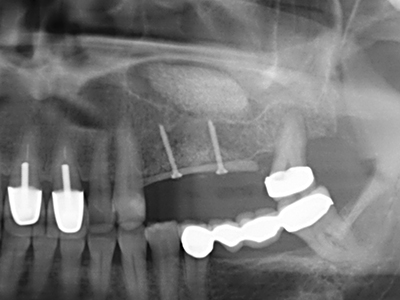

Когато се извършват хирургични процедури върху кост в непосредствена близост до чувствителни структури като кръвоносни съдове или нерви, ротиращите инструменти създават значителен риск за ятрогенно нараняване. Пиезоелектрическите апарати могат да бъдат от помощ при препарация на костно покритие и отстраняване на твърда кост близо до нерви, особено за оголване на нервите след ятрогенно нараняване, както и по време на латерализация на нервите за резекционни и реконструктивни процедури или поставяне на имплант (Фиг. 17-20). Лекият контакт между пиезонакрайника и нерва по принцип не води до нараняване, но ако действате непредпазливо с трионообразни движения или приставки за остатъчен костен субстрат, може да причините временно или перманентно увреждане на нерва. Въпреки това, рискът от увреждане се счита за много по-малък, отколкото при употреба на триони или ротиращи инструменти (Pereira, Gealh et al. 2014).